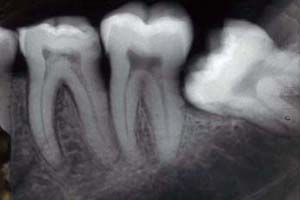

Tooth 18 (refer to the chart) which is my farthest back molar on my left lower jaw….is impacted…which basically means it’s growing like this (not my xray):

Part of the tooth is visible, but most of it is below the gum. It’s hard to keep clean, impossible to floss, and prevents me from chewing anything too tough on that side. Doesn’t really “bother” me because it’s been that way my whole life, but it’s certainly not “easy” to live with either.